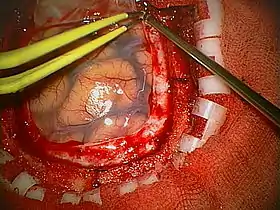

A craniotomy is a surgical operation in which a bone flap is temporarily removed from the skull to access the brain. Craniotomies are often critical operations, performed on patients who are suffering from brain lesions, such as tumors, blood clots, removal of foreign bodies such as bullets, or traumatic brain injury (TBI), and can also allow doctors to surgically implant devices, such as deep brain stimulators for the treatment of Parkinson's disease, epilepsy, and cerebellar tremor. The procedure is also used in epilepsy surgery to remove the parts of the brain that are causing epilepsy.

Human craniotomy is usually performed under general anesthesia but can be also done with the patient awake using a local anaesthetic; the procedure, typically, does not involve significant discomfort for the patient. In general, a craniotomy will be preceded by an MRI scan which provides an image of the brain that the surgeon uses to plan the precise location for bone removal and the appropriate angle of access to the relevant brain areas. The amount of skull that needs to be removed depends on the type of surgery being performed. The bone flap is mostly removed with the help of a cranial drill and a craniotome, then replaced using titanium plates and screws or another form of fixation (wire, suture, etc.) after completion of the surgical procedure. In the event the host bone does not accept its replacement an artificial piece of skull, often made of PEEK, is substituted. (The PEEK appliance is routinely modeled by a CNC machine capable of accepting a high resolution MRI computer file in order to provide a very close fit, in an effort to minimize fitment issues, and therefore minimizing the duration of the cranial surgery.)